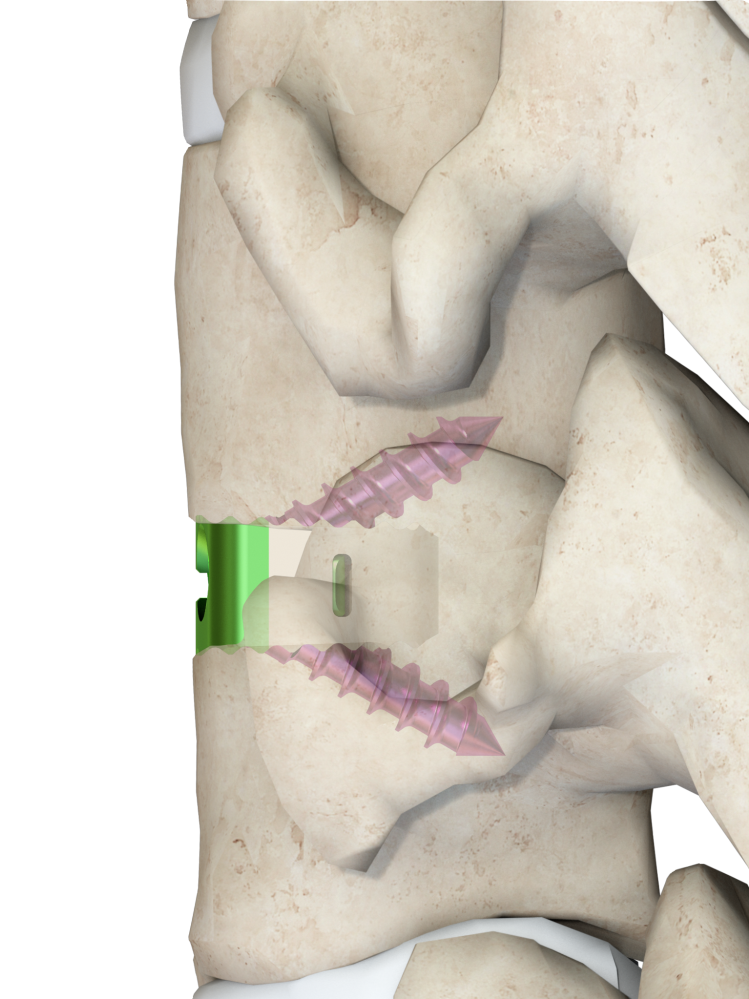

可靠的固定效果,提高初始穩(wěn)定型和遠期融合效果

Φ3.5×8/10/12/14mm Φ4.0×8/10/12/14mm